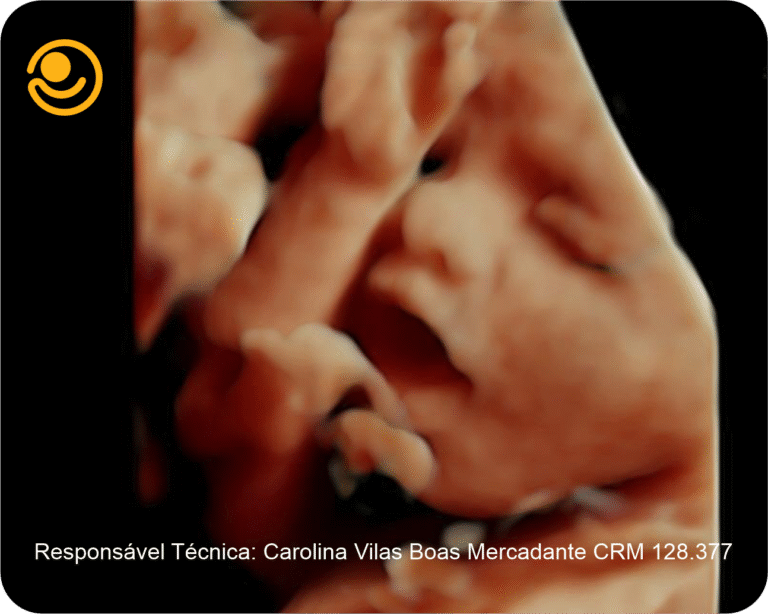

3D / 4D Live – Maior realismo nas imagens e mais precisão nos diagnósticos.

Imagens 3D / 4D

✓ Ultrassonografia 3D/ 4D com imagem em HD